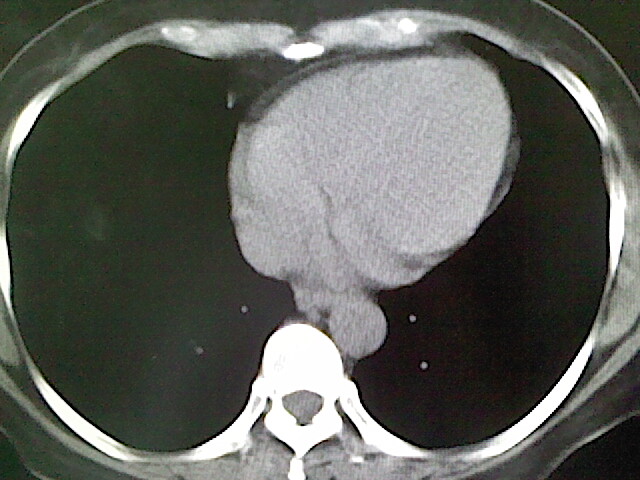

女,52岁,咳嗽,咳痰多日

左下肺陈旧纤维索条!

左肺舌段炎性改变

我见过几例,为炎症后纤维条索

慢性炎症后改变

考虑慢性炎性病灶粘连牵拉改变。

左肺舌叶纤维锁条病变。

左肺上叶下舌段炎症并局部胸膜反应。

左肺舌叶纤维索条影。

左肺舌叶段陈旧性病变

左肺舌段炎性反应。片子的质量太不好了。

左肺舌段炎性

炎性改变

左肺舌叶纤维索条影